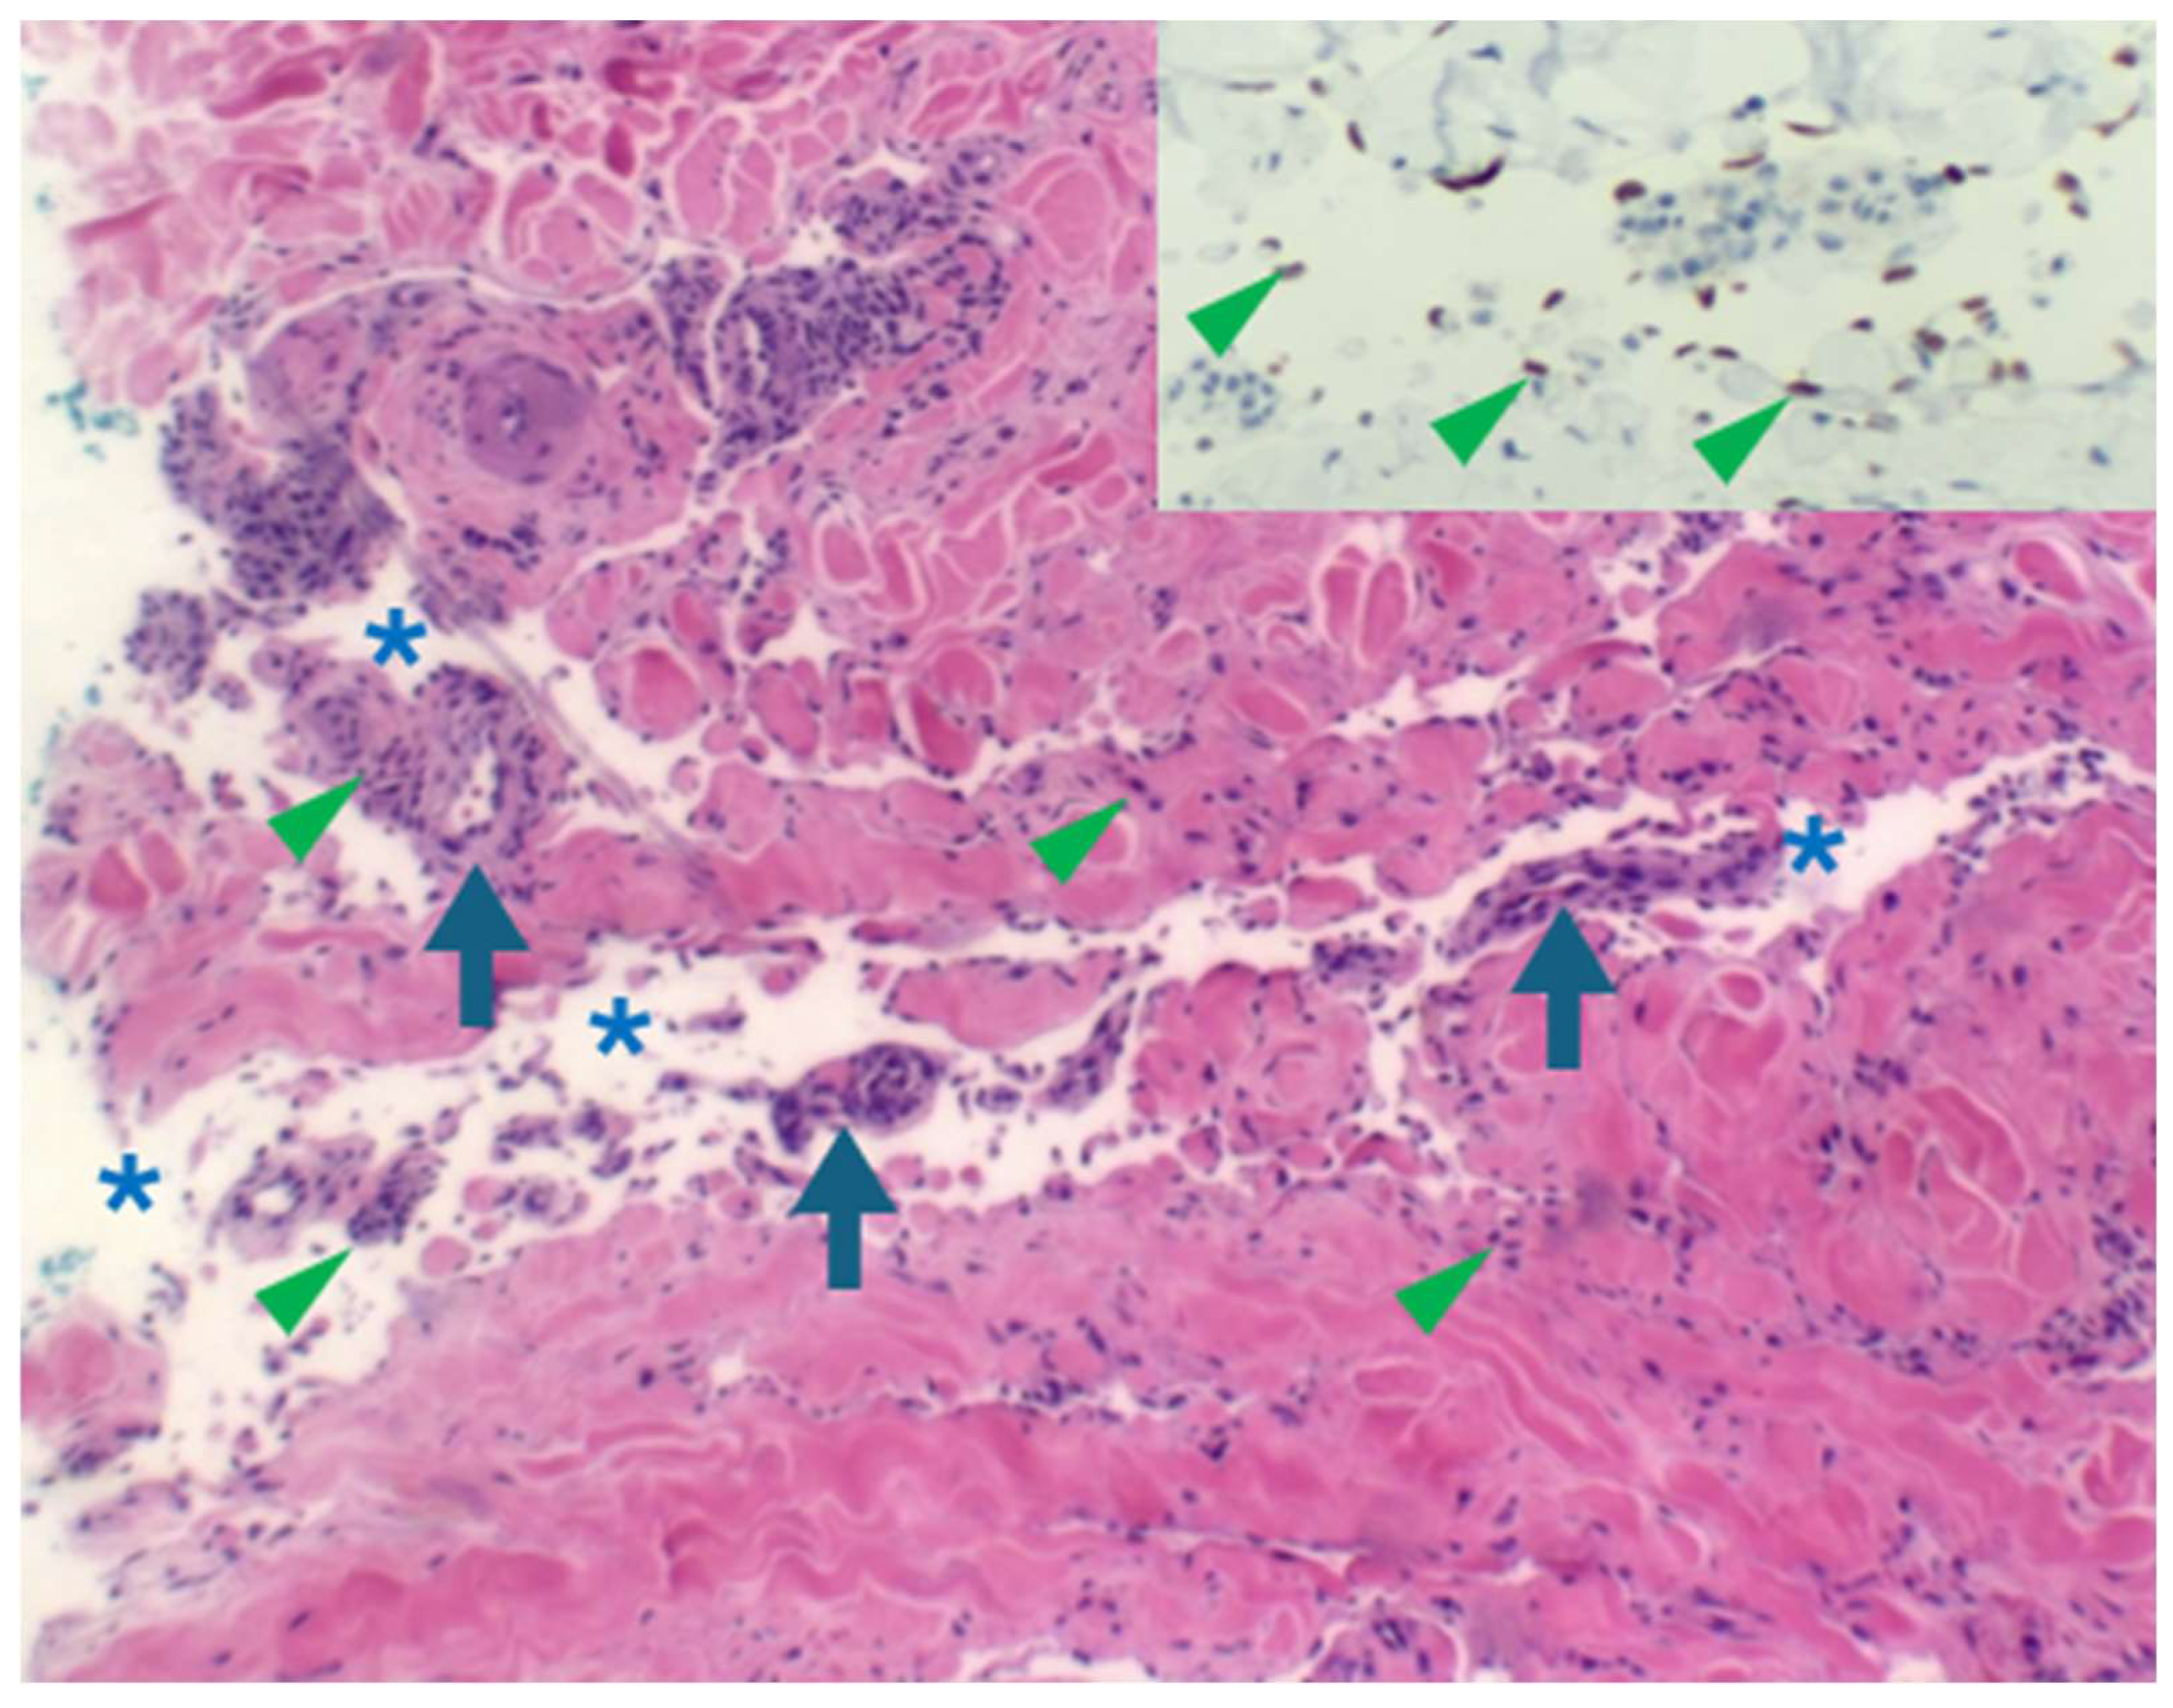

5.3. HHV8 and KS: Diagnostic Traps and Pitfalls

Furthermore, HHV8 IHC is also diagnostically invaluable in navigating through potential diagnostic pitfalls and traps. Acroangiodermatitis, also known as stasis dermatitis, is characterised by the presence of oedema, variable fibrosis, granulation tissue with spindle cells and capillaries, and variable haemosiderin pigment deposition (Figure 7A,B). These features are also shared by KS. Distinguishing KS from acroangiodermatitis is critically dependent on positive HHV8 immunohistochemical staining (Figure 7B inset). Pyogenic granuloma-like KS has recently emerged as a distinct KS subtype. The raised erythematous polypoid appearance and the microscopic vascular proliferation (Figure 7C) with focal solid cellular foci may mimic pyogenic granuloma (PG). HHV8 immunonegativity (Figure 7D) underpins the diagnosis of PG and distinction from PG-like KS. PG is a reactive vascular proliferation that undergoes spontaneous regression.